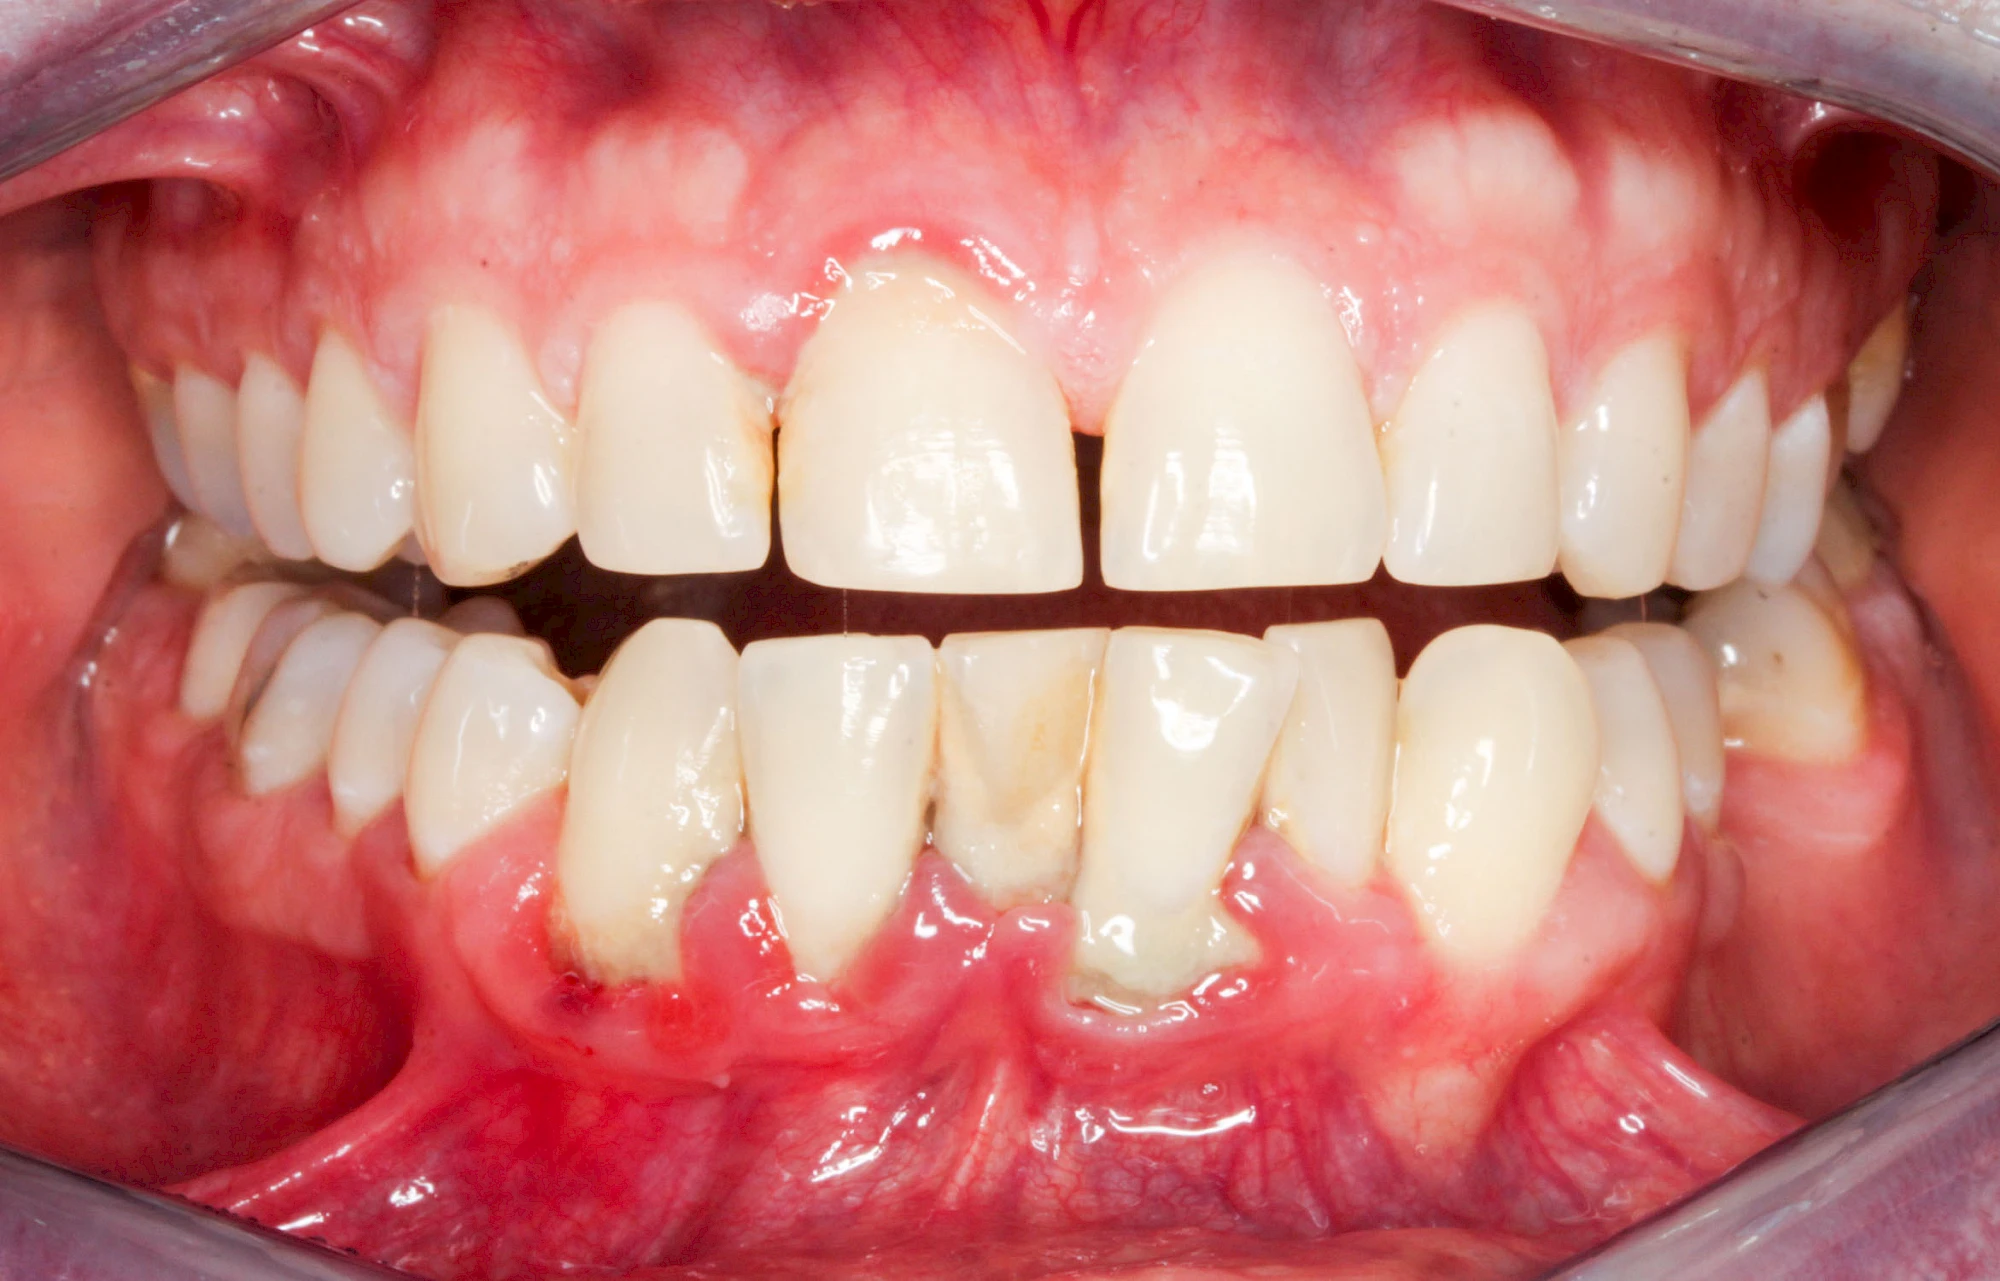

Bakterien in den Zahnbelägen greifen neben den Zähnen auch das Zahnfleisch (Gingiva) und den gesamten Zahnhalteapparat (Parodont) an. Der Körper reagiert mit einer Entzündung, sichtbar als Rötung und Schwellung. Meist blutet das Zahnfleisch z .B. beim Essen oder auch beim Putzen der Zähne.

Ist zunächst nur das Zahnfleisch von der Entzündung betroffen, spricht man von Gingivitis. Später, wenn auch der Knochen um die Zähne herum entzündet ist, spricht man von einer Parodontitis. Bei der Parodontitis wird der Knochen nach und nach abgebaut und das Zahnfleisch zieht sich zurück. Die Zahnhälse und Zahnwurzeloberflächen liegen mehr und mehr frei. Die Zähne werden zunehmend lockerer und fallen schließlich aus.

Bei Schwellung, Rötung oder Blutung des Zahnfleisches sollte neben der Intensivierung und Optimierung der Mundhyiene der Zahnarzt kontaktiert werden.